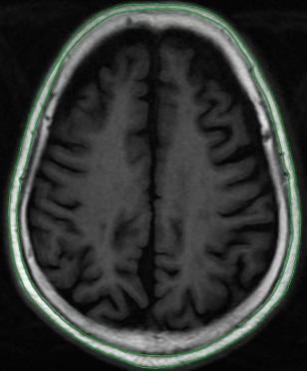

| 图3 磁共振轴位SE T1WI图像及头皮下脂肪区域勾画示意图 |

| Fig. 3 Magnetic resonance axial SE T1WI image and a schematic diagram outlining the subcutaneous fat area |